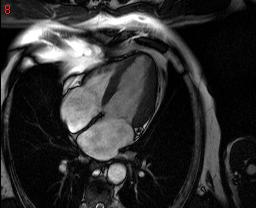

cardiac mri is some thing which can save many lives but the software available to analyse them are too costly...

the pictures show a few cardiac MRI data.. is there any way we can crop out hust the heart ,

itried a few thresholding scheles but, they dont seem to work very well